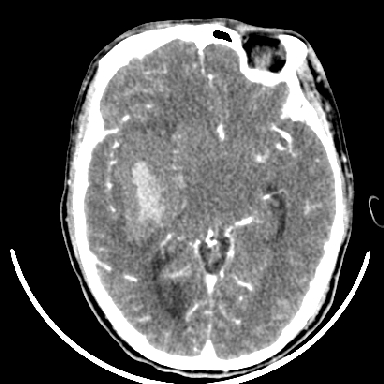

标题: CT6056:脑出血(血管畸形?) [打印本页]

标题: CT6056:脑出血(血管畸形?)

m 40突发头痛左侧偏瘫3小时

考虑高血压性脑出血,依据:

1是高血压性脑出血的好发部位,形态呈肾形,是高血压性脑出血的常见形状

2增强时占位效应加重了,考虑出血还没有停止

3病灶周围水肿不是太厉害,一般肿瘤出血水肿多非常明显

4病灶周围的‘软组织’影没有明显的强化

5至于脑血管畸形引起的出血,暂时没有看到明显的畸形血管影,也不太支持

支持右侧基底节脑出血

右侧基底节区脑出血.

支持右侧基底节区(主要为外囊区)原发性脑出血。

另附部分资料:“血液溢出血管外形成血肿,其内含有大量血红蛋白、血浆白蛋白,球蛋白,因这些蛋白对x线的吸收系数高于脑质,故ct呈现高密度阴影,ct值达40~90h,最初高密度灶呈非均匀一致性,中心密度更高,新鲜出血灶边缘不清。基底节区血肿多为“肾”型,内侧凹陷,外侧膨隆,因外侧裂阻力较小,故向外凸,其它部位血肿多呈尖圆形或不规则形”

术中抽出40ml陈旧血液,血肿底部似见一条索血管影